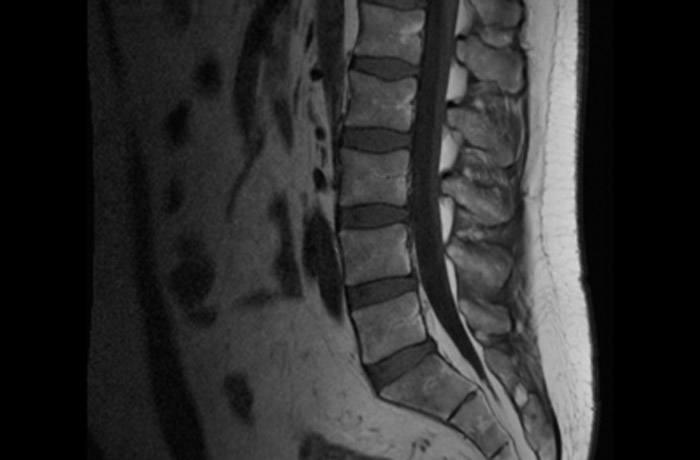

МРТ поясничного отдела позвоночника

МРТ поясничного отдела позвоночника — диагностическая процедура по выявлению патологических нарушений и процессов, возникающих вследствие травм или развития заболеваний. Преимуществом магнитно-резонансной томографии является максимальная информативность, детальное обследование любой зоны и почти полное отсутствие противопоказаний.

В результате диагностики могут быть выявлены заболевания: рассеянный склероз, гемангиома младенческая, инфекционное поражение, миелит, остеопороз, скрытые травмы, метастазы, новообразования, спинальный стеноз и другие.